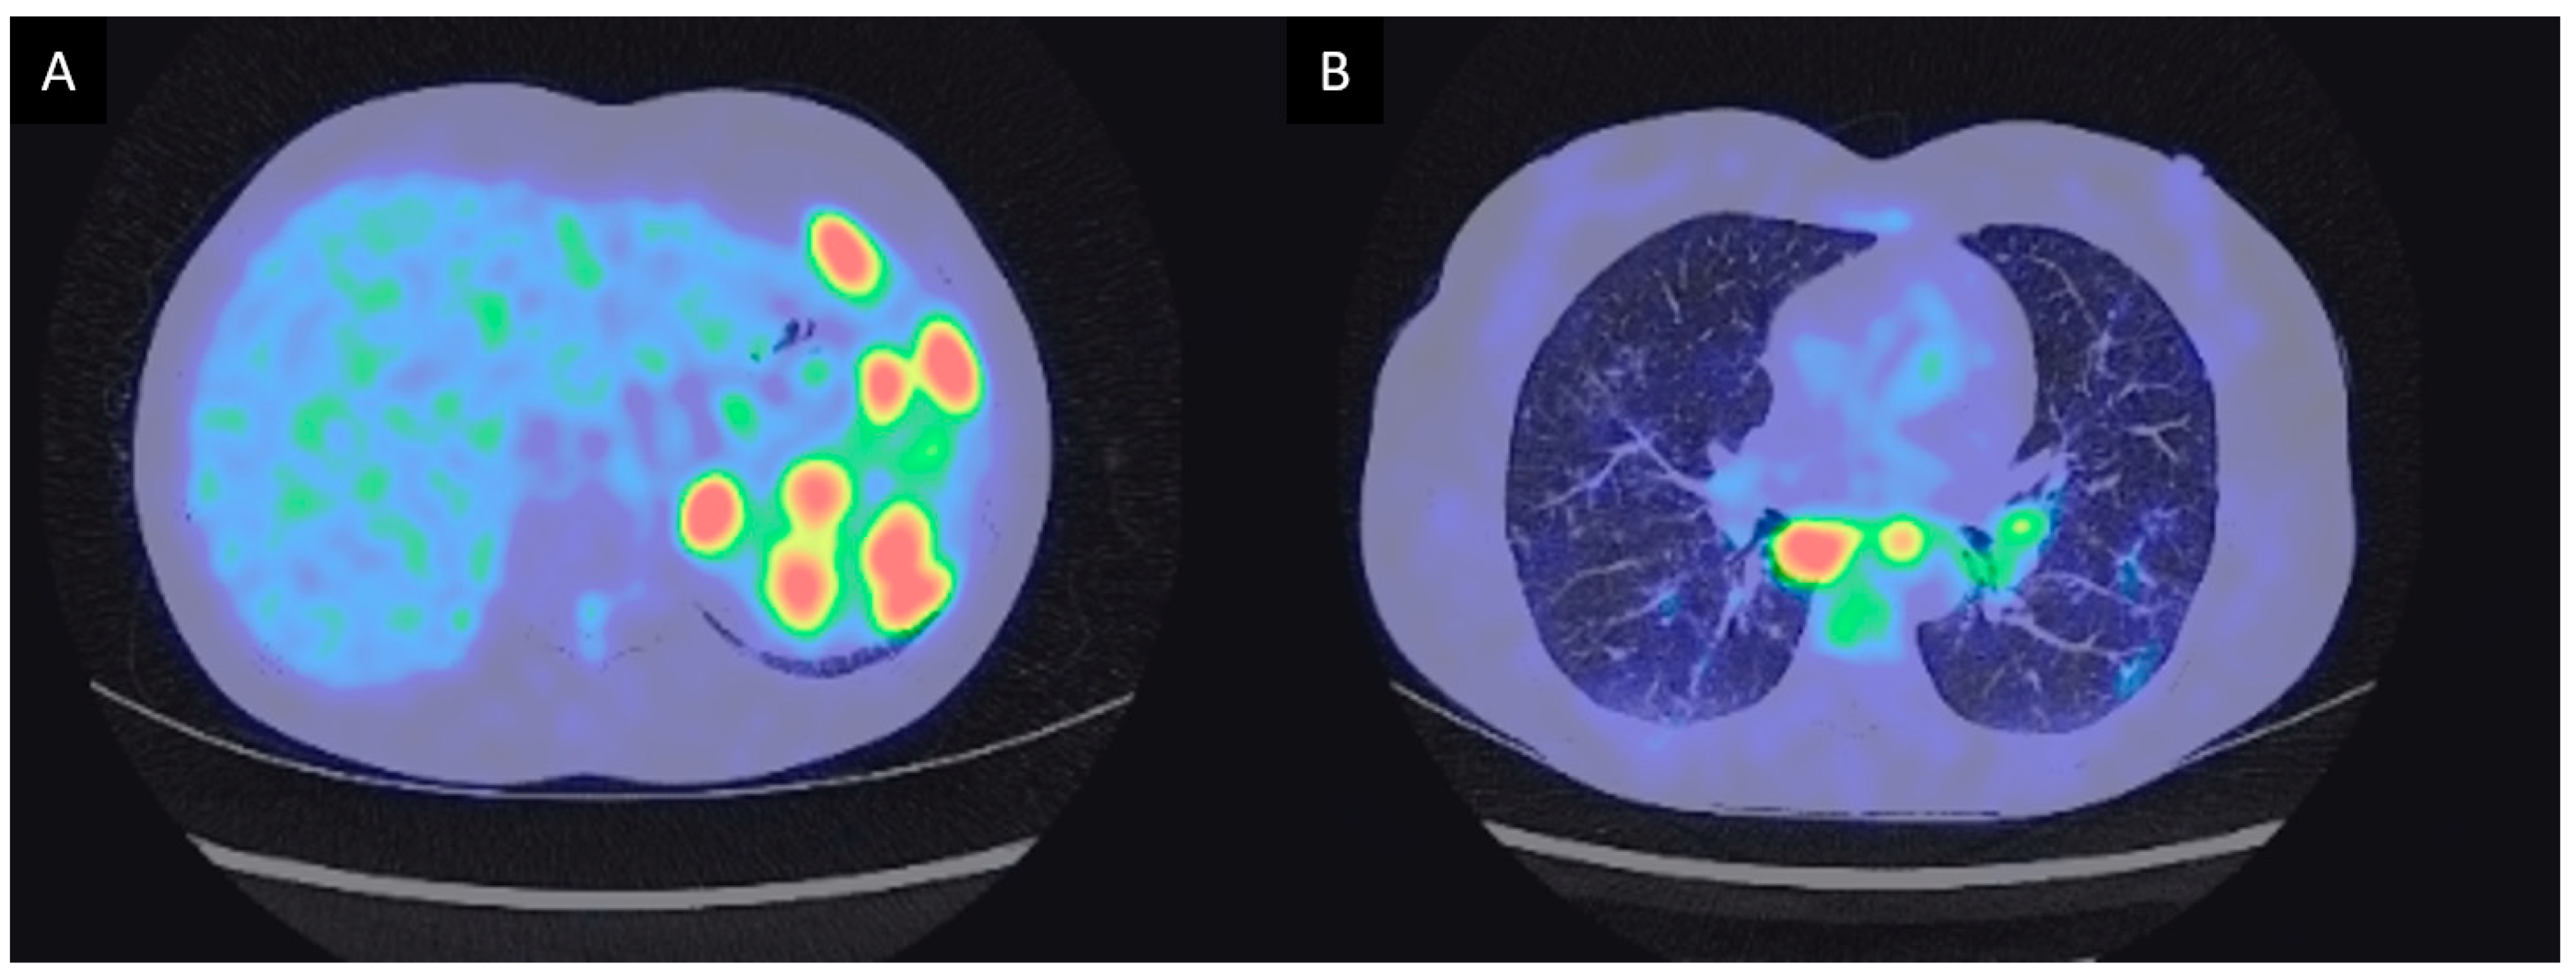

3.2.1. Case Description

| 3 | M | 45 | Maghrebian | Altered general condition with 2 kg weight loss. Hard, fixed and painless left sus clavicular and cervical adenopathies. Sino nasal obstruction with retropharyngeal adenopathies with cavum mucosal thickening | Atypical lymphadenopathies, exclusive extrathoracic multi organ involvement. | 24 months | Hodgkin’s lymphoma | Chemotherapy (ABVD, ICE) | Currently continuing chemotherapy |

| 4 | F | 56 | Caucasian | Cervical and axilar lymph nodes. Cavum tumefaction. Granulomas without atypical features. Atypical CD30+ cells on repeated lymph nodes sampling. | Cavum infiltration and exclusive extrathoracic lymph nodes. | 72 months | Biclonal lymphoma (Hodgkin and Diffuse large B cell lymphoma). Hodgkin disease was already present at disease onset 6 years before (second-look histological examination). | Chemotherapy (R-CHOP 8x) | Healing |

| 5 | M | 54 | Maghrebian | Lower esophagus stenosis with peri esophageal adenopathies and dysphagia. Paratracheal and subcarinal and antero superior mediastinal lymph nodes. Histological examination concordant with Piringer Kuchinka’s lymphadenitis. | Compressive phenomenon. No hilar lymph nodes with anterior mediastinal lymph nodes. | 40 months | EBV positive Hodgkin’s lymphoma | ABVD 6 courses | Healing |

| 6 | M | 75 | Hispanic | Compressive right orbital infiltrate. Isolated enlarged lymph node of Barety area. | Compressive phenomenon. Isolated mediastinal lymph node without hilar lymph node. | 17 months | Right oribtal marginal zone lymphoma (previously improved by local corticosteroids more than a year before for suspected scleritis). | Surgical resection. | Healing |